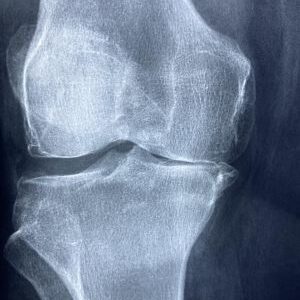

Z březnové Meduňky: Jak se rychle dostat do kondice

Aktuální březnová Meduňka, která vyšla minulý týden, přináší kromě jiného spoustu návodů na to, jak po zimním čase obnovit, podpořit či znovu „nastartovat“ životní sílu. Blížící se jaro už se hlásí o slovo, a tak můžeme třeba začít s přiměřeným cvičením nebo se vydat do přírody – to vše nám pomůže se opět dostat do formy, která – přiznejme si – u většiny z nás v zimě trochu utrpěla… -:) Inspirací může být například článek fyzioterapeuta Mgr. Pavla Klouda (…tento článek je součástí hlavního tématu březnového čísla Meduňky – emedunka.cz ) Po dlouhé zimě, kdy většina z nás sportuje mnohem méně než v letních měsících, je důležité získat zase co…